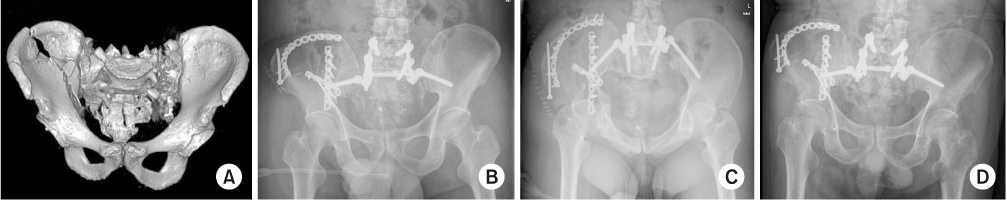

Fig. 8

(A–C) A 63-year-old male sustained an unstable pelvic injury with spino-pelvic dissociation. (B, C) The spino-pelvic fixation was performed and showed the iliac screw, which was used with the connecting rod. (D) The radiograph after 12 months showed the maintenance of pelvic ring.